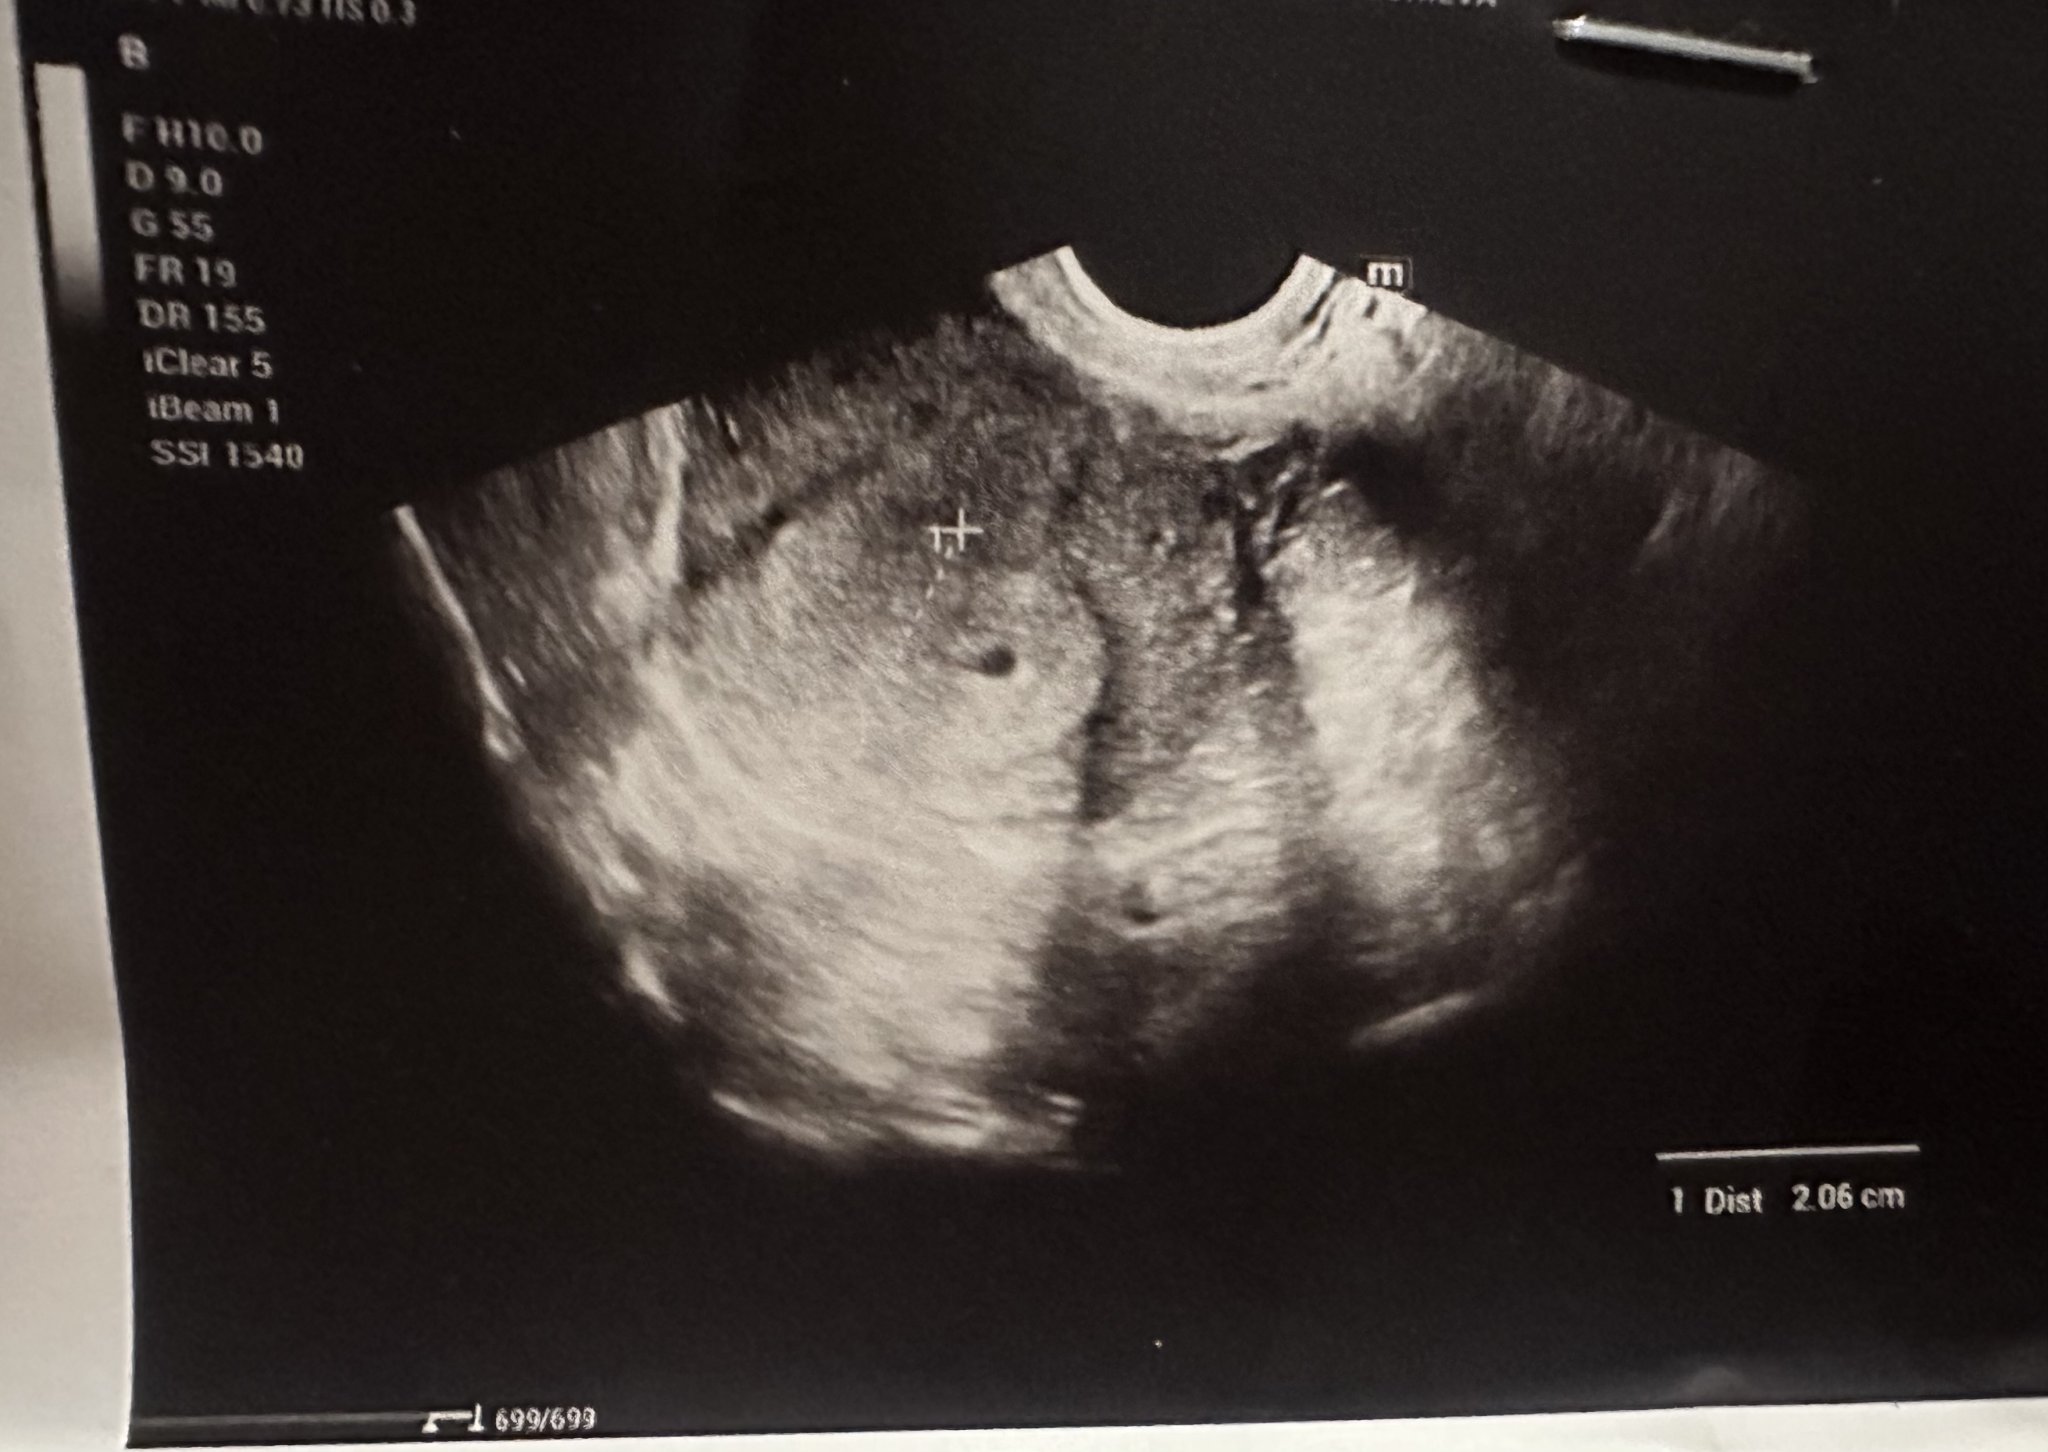

Здравейте, момичета! Имам нужда от вашата помощ. Днес бях на преглед за потвърждение на бременност, потвърдена е... Но доктора беше изключително груб, не ме гледа вагинално, само коремно, не ми каза в коя седмица съм. Каза че не вижда ембрион, а на мен сякаш ми се вижда. Последния цикъл ми беше на 28 август. Моля, дайте вашето мнение относно седмиците и снимката.